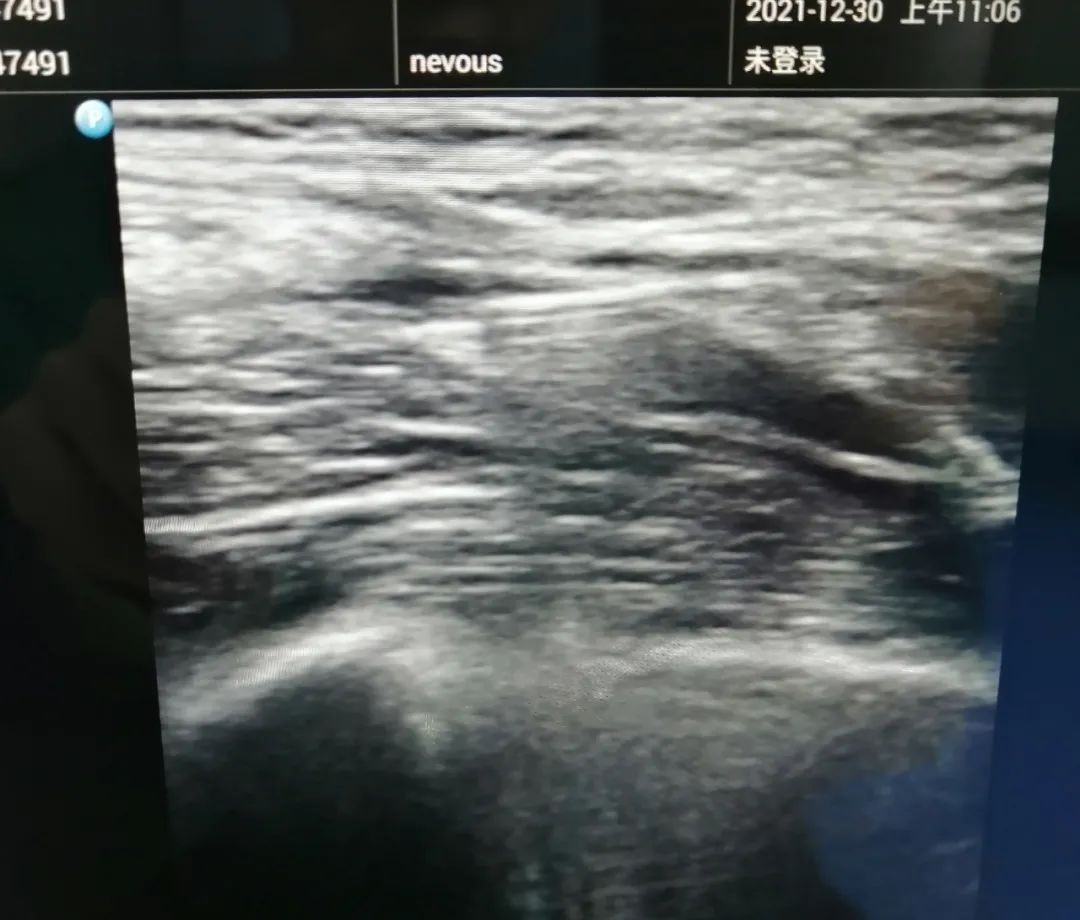

B超引导下髂筋膜阻滞

髂筋膜间隙是一个潜在的腔隙,其后方以髂腰肌为界,前方以髂筋膜为界,髂筋膜浅层以阔筋膜覆盖。股神经和股外侧皮神经、闭孔神经在骨盆节段都位于髂筋膜下方。髂筋膜间隙阻滞是相对简单的技术,可以作为股神经阻滞或腰丛阻滞的补充。因此,在髂筋膜下注射足量的局麻药,即使位置离神经较远,局麻药也可在髂筋膜下方扩散,到达这些神经。